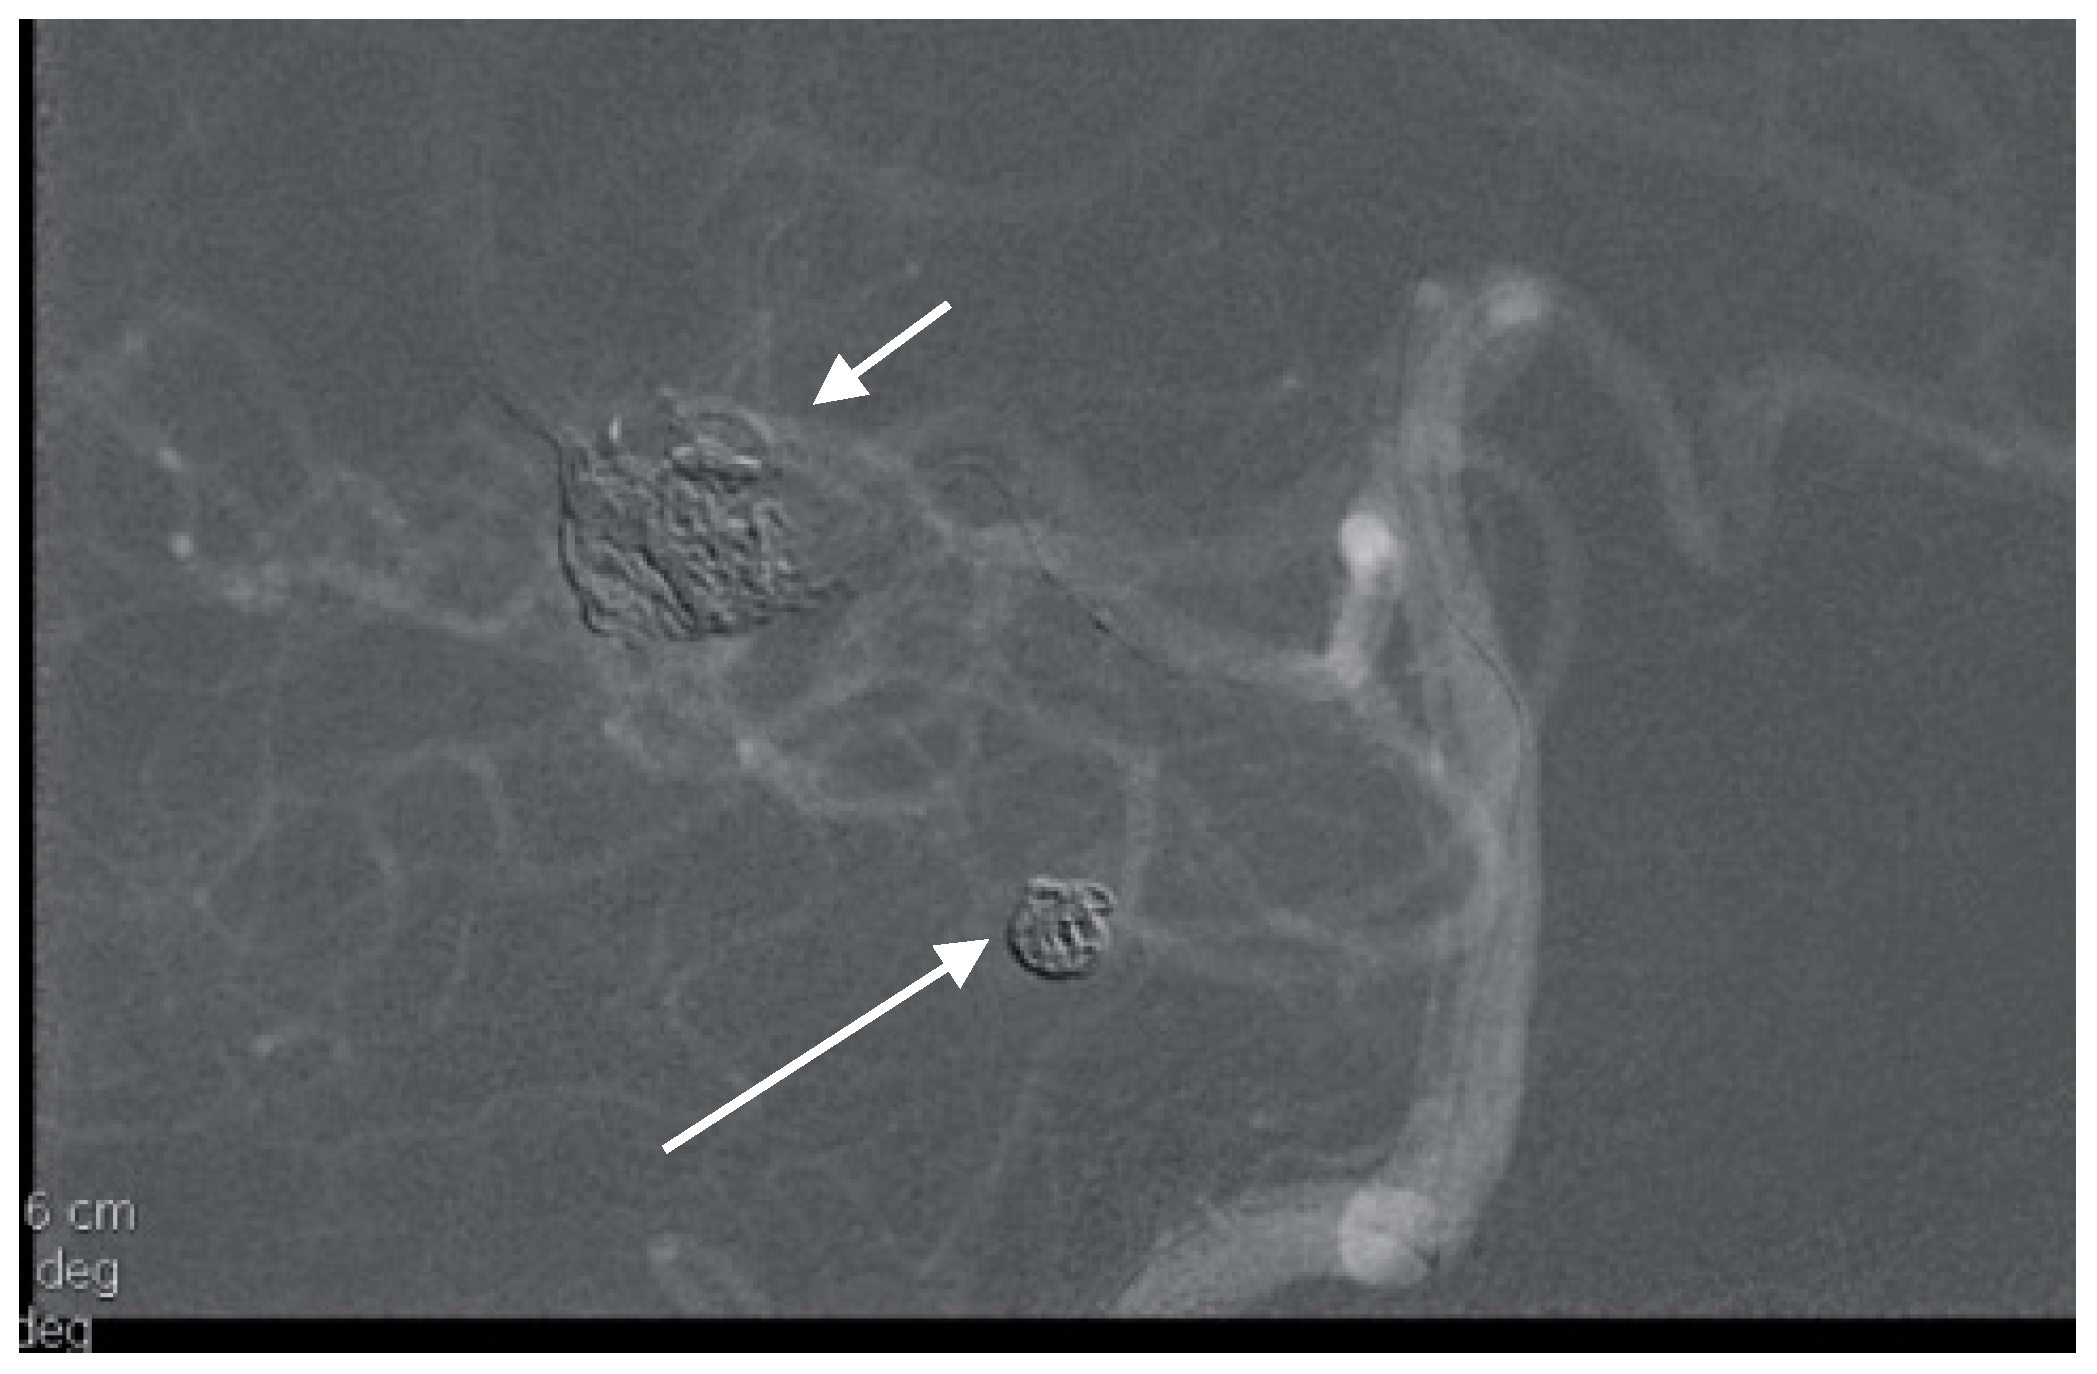

A 52-year-old woman presented with atypical headaches on an acute stage. MRI and subsequent PAG revealed an AVM of the cerebellar convexity with three aneurysms on parent arteries at the SCA and AICA bifurcations (Figure 3). The patient was treated by microsurgical clipping and resection of the AVM. Her postoperative course was uneventful, and follow-ups are undertaken every year.

Figure 3. Multiple superior cerebellar artery (SCA) and AICA aneurysms along with cortical arteriovenous malformation (AVM) of the cerebellum on lateral angiogram highlighted with arrows.